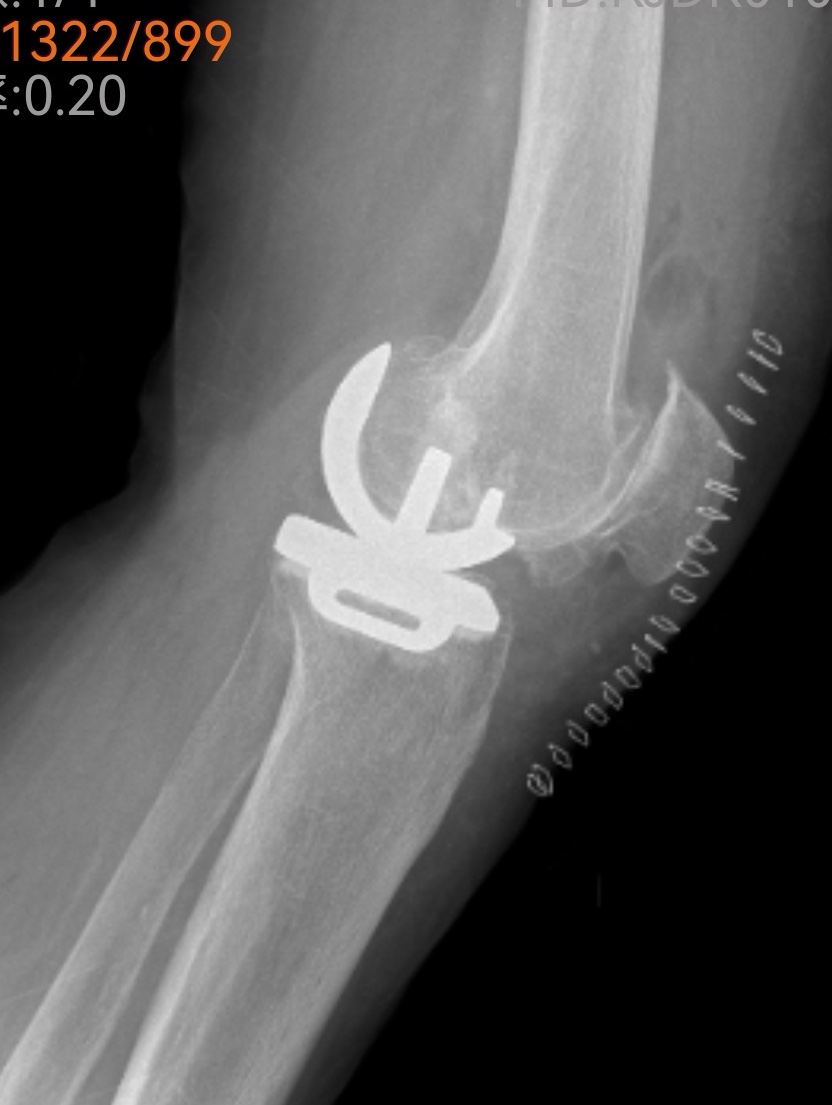

傳統(tǒng)的全膝關(guān)節(jié)置換固然能解決問題,但創(chuàng)傷較大、恢復(fù)期長。經(jīng)過團(tuán)隊(duì)綜合評估,魏海清主任提出了一個(gè)更精細(xì)的方案:“我們建議行左膝關(guān)節(jié)單髁置換術(shù)。這就像牙齒壞了,我們不必把所有牙齒都換掉,而是只替換損壞的部分。這種手術(shù)只替換磨損的軟骨和部分骨質(zhì),能最大限度保留健康組織。”他拿出膝關(guān)節(jié)模型,耐心地向一家人解釋手術(shù)原理:“您看,膝關(guān)節(jié)分為內(nèi)側(cè)、外側(cè)和髕股三個(gè)部分。您的磨損主要集中在內(nèi)側(cè),所以我們只需置換這一部分。”這種個(gè)體化、精準(zhǔn)化的治療理念,讓原本忐忑的一家人逐漸安心。

手術(shù)室里,骨科、麻醉科、手術(shù)室團(tuán)隊(duì)配合默契。微創(chuàng)切口僅有傳統(tǒng)手術(shù)的一半大小,精細(xì)的操作在關(guān)節(jié)鏡輔助下進(jìn)行。沒有大刀闊斧的創(chuàng)傷,只有精準(zhǔn)細(xì)致的重建。一小時(shí)后,手術(shù)順利結(jié)束,出血量僅約100毫升。“這么快?”等候在外的兒子們幾乎不敢相信。魏海清主任走出手術(shù)室,微笑點(diǎn)頭:“很順利,單髁置換本來就是微創(chuàng)手術(shù),對患者損傷小。”